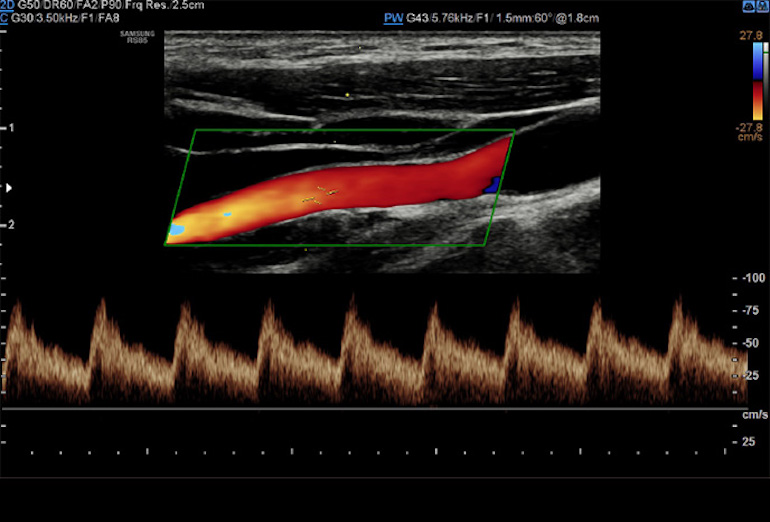

Dentre os exames de ultrassonografia, os exames Doppler se caracterizam por avaliar de forma específica detalhes do sistema circulatório, de forma não invasiva, ou seja, sem uso de medicamentos, meios de contraste, sem uso de radiação, e sem necessidade de sedação ou internação hospitalar, de forma indolor e sem efeitos colaterais, podendo ser realizado inclusive em gestantes para avaliação do bem estar do feto. Um dos principais benefícios dos exames Doppler é justamente a avaliação da saúde fetal, quando o médico examina principalmente as artérias do cérebro fetal, do cordão umbilical e também as artérias uterinas. Com base nos dados obtidos, é possível prever, por exemplo, a chançe da gestante desenvolver hipertensão gestacional, bem como se o feto está recebendo pelo cordão umbilical a oxigenação necessária, ou se há algum sinal sugestivo de redução da oxigenação cerebral. Algumas vezes pode ser preciso, caso a circulação fetal esteja muito comprometida, realizar o parto antes da data prevista, e o exame Doppler obstétrico é fundamental para auxiliar na decisão da melhor hora para a intervenção do médico obstetra. Nas áreas de cardiologia, neurologia e cirurgia vascular, a aplicação do exame Doppler é ampla. Os exames mais realizados são o Doppler de carótidas e vertebrais (artérias da região do pescoço que cursam para o cérebro), e o doppler de membros inferiores, tanto para avaliação de trombose, varizes e redução da circulação arterial. Nesses casos, o exame auxilia o médico assistente na análise de placas ateromatosas (depósitos de colesterol e calcificações), bem como se o fluxo sanguíneo está suficiente ou insuficiente para os órgãos específicos, ou ainda se há alguma trombose venosa ou oclusão das artérias. No caso das varizes, o exame detalha a anatomia venosa, bem como onde a causa das veias dilatadas se inicia, as veias insuficientes, o trajeto varicoso, e é fundamental para o planejamento e escolha da técnica cirúrgica, reduzindo de forma significativa o índice de recidivas e complicações pós-operatórias. O exame Doppler é também realizado na diferenciação de lesões de outros órgãos, como na tireóide e na mama, e tem grande importância na avaliação de órgãos pré e pós transplantes, como por exemplo do fígado e dos rins.